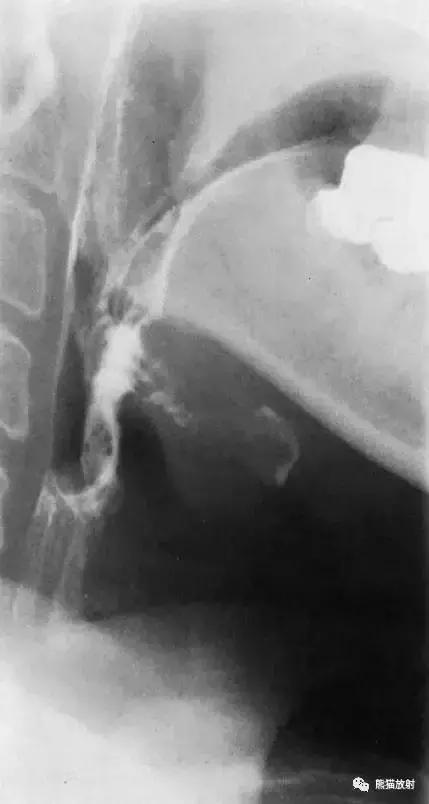

二、下咽部(侧位)

图3 下咽部造影(侧位)

图4 下咽部解剖(侧位)示意图。1 悬雍垂,2 颈椎,3 舌,4 口咽,5 下颌骨,6 会厌谷,7 喉咽,8 舌骨,9 梨状隐窝,10 喉室,11 食管,12 气管